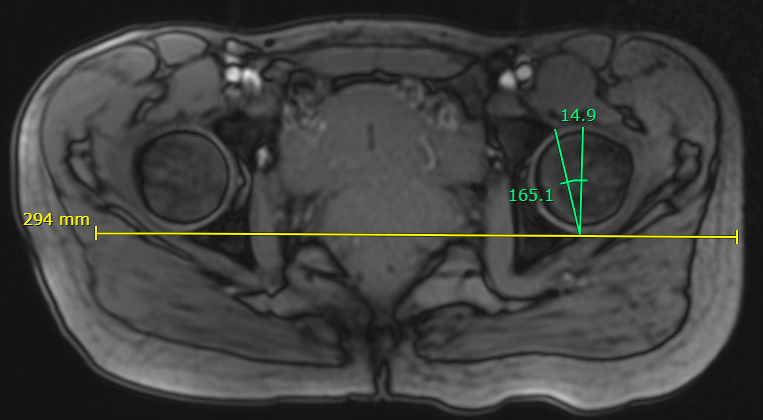

Lateral centre edge angle (LCEA)

Measurement

- vertical line drawn from the center of the femoral head

- line from the center of the femoral head to the lateral acetabular rim

- normal 20 - 40 degrees

- dysplasia < 20 degrees

- profunda > 40 degrees

Increased LCEA in profunda